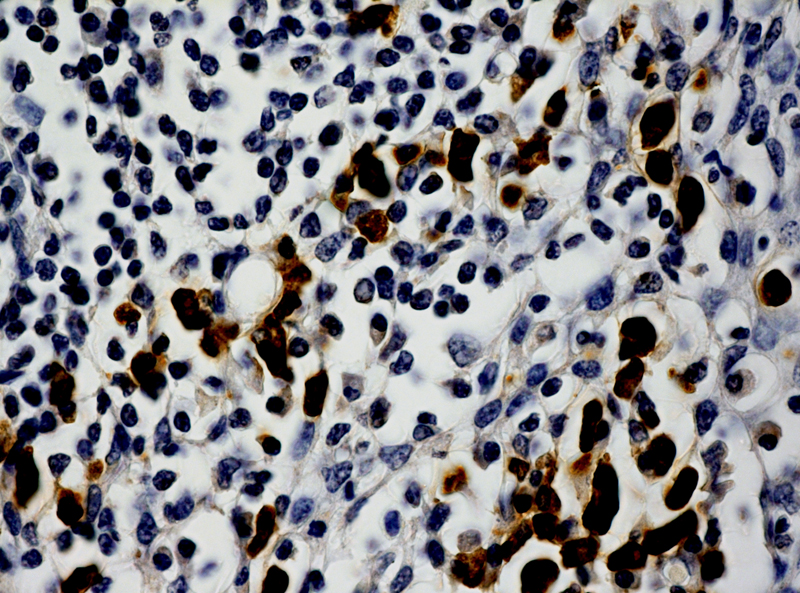

Human papillomaviruses (HPVs) induce a variety of proliferation lesions, leading to onset of squamous cell carcinoma (SCC) of the various tissues. HPV type 16 and 18 are responsible for about 70% of cervical cancer cases. We offers fluorescein labeled HPV probes for specific detection of HPV 16 and 18 genotype. The probes allow the localization of specific HPV viral DNA sequences in cultured cell lines,

cytopathology specimens, and FFPE tissue sections. It is the only method permitting detection of HPV viral DNA in a morphological context. Combined with the super sensitive ISH Detection systems, the probes offer reliable, highly sensitive and easy-to-perform assays.